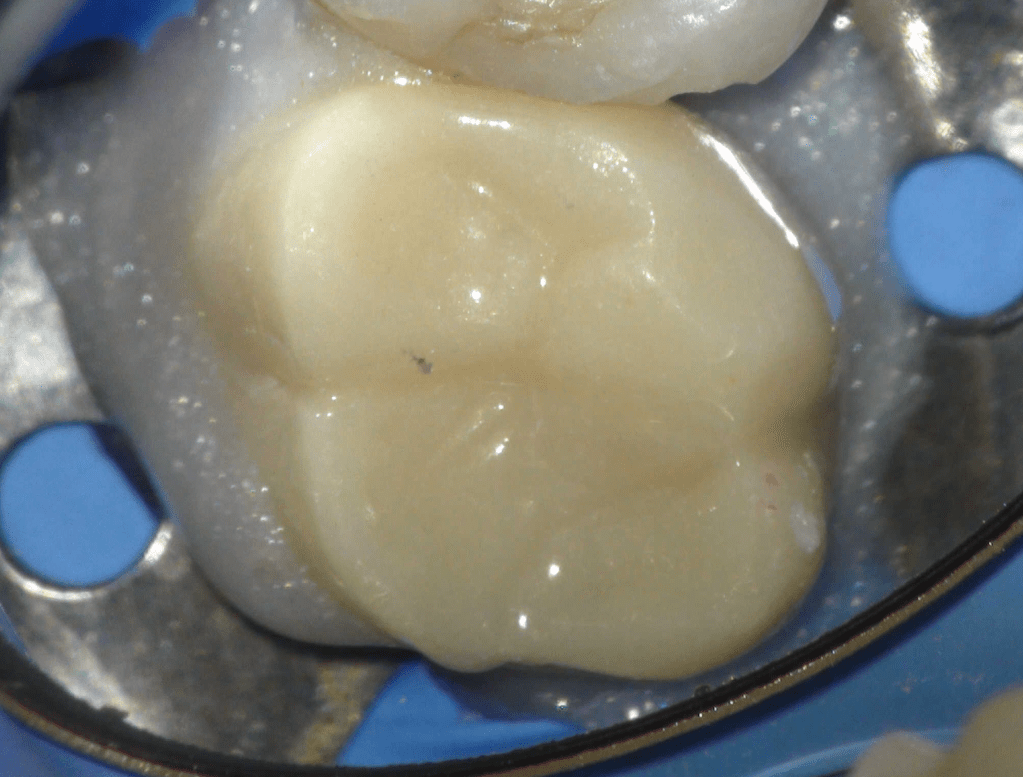

Molar superior